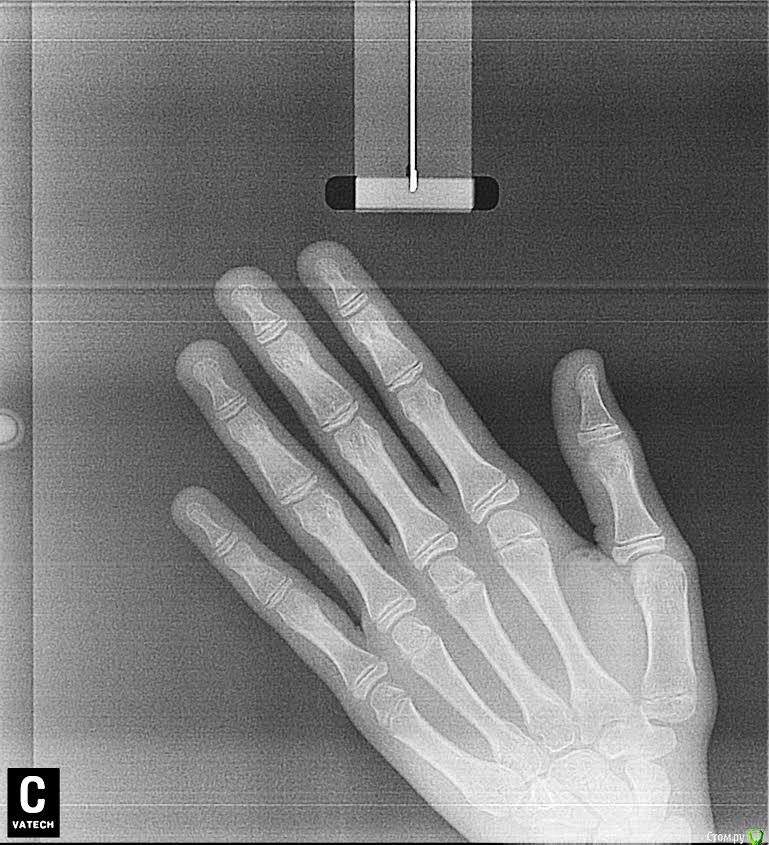

Мама пациента Опубликовано 20 мая, 2016 Поделиться Опубликовано 20 мая, 2016 Письмо на форум стоматологов. Здравствуйте, уважаемые доктора. Извините за много букв, но короче не расскажешь. Дочери 12 лет. Никогда не замечала перекрёстного прикуса, вдруг в июне 2015 г. на регулярном осмотре терапевт сказала, что прикус перекрестный, нужно срочно бежать к ортодонту, а то ребенок «съест» зубы, хотя раньше не говорили об этом. Видимо поспешили с выбором врача. Доктор хорошая, старательная, молодая, но видимо у нас не совсем линейная ситуация, с которой раньше она не сталкивалась. Здоровье, к сожалению, у ребенка не богатырское, парез лицевого нерва был с рождения, дисплазия соединительной ткани – исследованиями не подтвержденная (много гибкости, мало силы и упругости мышц). Поставили брекеты на верхние зубы в июле 2015- 11 лет. Нижнюю челюсть наклеили в ноябре. ОПГ снимок до того прилагается. Кроме него исследований не делали, теперь поняла, что надо было. Все поездки к врачу заканчиваются 3-х-5-ти дневными страданиями. В марте после поездки (наклеили клыки, прорезающиеся нижние 7-ки и поменяли дуги), на следующий день поднялась тем-ра 37,7 и потом 3 недели!!! она была субфебрильная. Анализы крови и м. были нормальные (немного снижены сегментоядерные и повышены лимфоциты). Это сопровождалось головокружением. Лечили синусит. По ВСД по назначению невропатолога сделали исследования (ЭЭГ, УЗДГ- ТГ)- повышено внутричерепное давление (результаты есть). Сделали 4 сеанса у мануального тер., который по его словам «снял блок с шеи…и сделал спину (убрал начинающийся сколиоз)». Головокружения прекратились. Сходили на консультации к хорошим ортодонтам в Москве, к сожалению, никто пока помочь не берется. После одной из консультаций (врач достаточно активно двигала челюсть) опять кружилась голова в течении пары часов. На консультации к челюсно-лицевым хирургам пока не попали, т.к. в Москве к гуру целая история попасть, а конец учебного года и два пропущеннных месяца в школе. Но операцию делать я ей не буду, т.к. риски для здоровья от операции гораздо выше. Будет взрослая сама решит. Случай не простой, время упущено, челюсть выросла криво, но рост еще идет (доктор сказал по ренгену ладони). Неужели в стране нет специалиста, который в комплексе занимается ортодонтией с содружестве в неврологами и мануальными (краниальными) терапевтами. Может кто-то занимается миотерапией (лечебная физкультура для челюстей). Сейчас просто боимся идти к ортодонту менять дуги и доклеивать отвалившиеся брекеты и я, и ребенок. Потому, что 4 недели мучений и по учебе уже пропустили пол-четверти. Ей хочется все бросить, оторвать все брекеты и забыть, как страшный сон. Хотя я прекрасно понимаю, что таким прикус оставлять нельзя, надо попытаться что-то сделать. Что бы вы делали для своего ребенка в этой ситуации? Ссылка на комментарий

Мама пациента Опубликовано 20 мая, 2016 Автор Поделиться Опубликовано 20 мая, 2016 Лицо и кисть Ссылка на комментарий